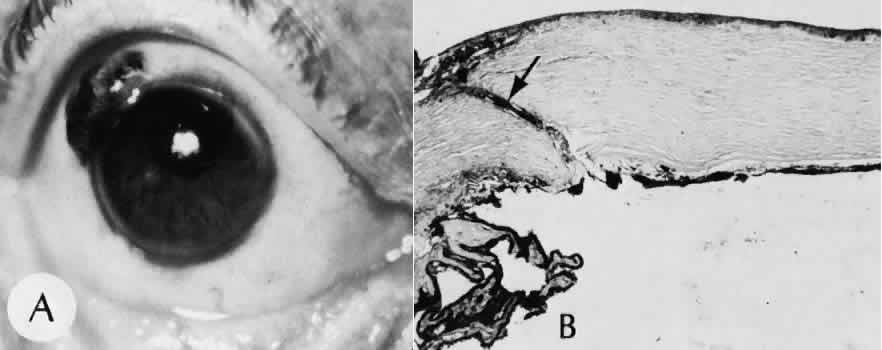

SCLERAL HEALING

The sclera itself does not participate directly in wound healing. Partial-thickness injuries are healed by formation of granulation tissue from the epi-scleral tissue in external wounds or from uveal tissue in internal wounds (Fig. 8). Full-thickness defects of the sclera heal by granulation tissue originating in the episcleral tissue and uveal tract. Mitomycin is used in filtering procedures specifically to prevent the formation of granulation tissue and promote establishment of an aqueous fistula.30

Fig. 8. Following a scleral incision, granulation tissue from episcleral tissue (E) and uveal tissue (U) will proliferate through the full extent of the sclera. The tissue will remodel along tension lines to reapproximate the tensile strength of the original tissue (Hematoxylin-eosin stain; × 28.)